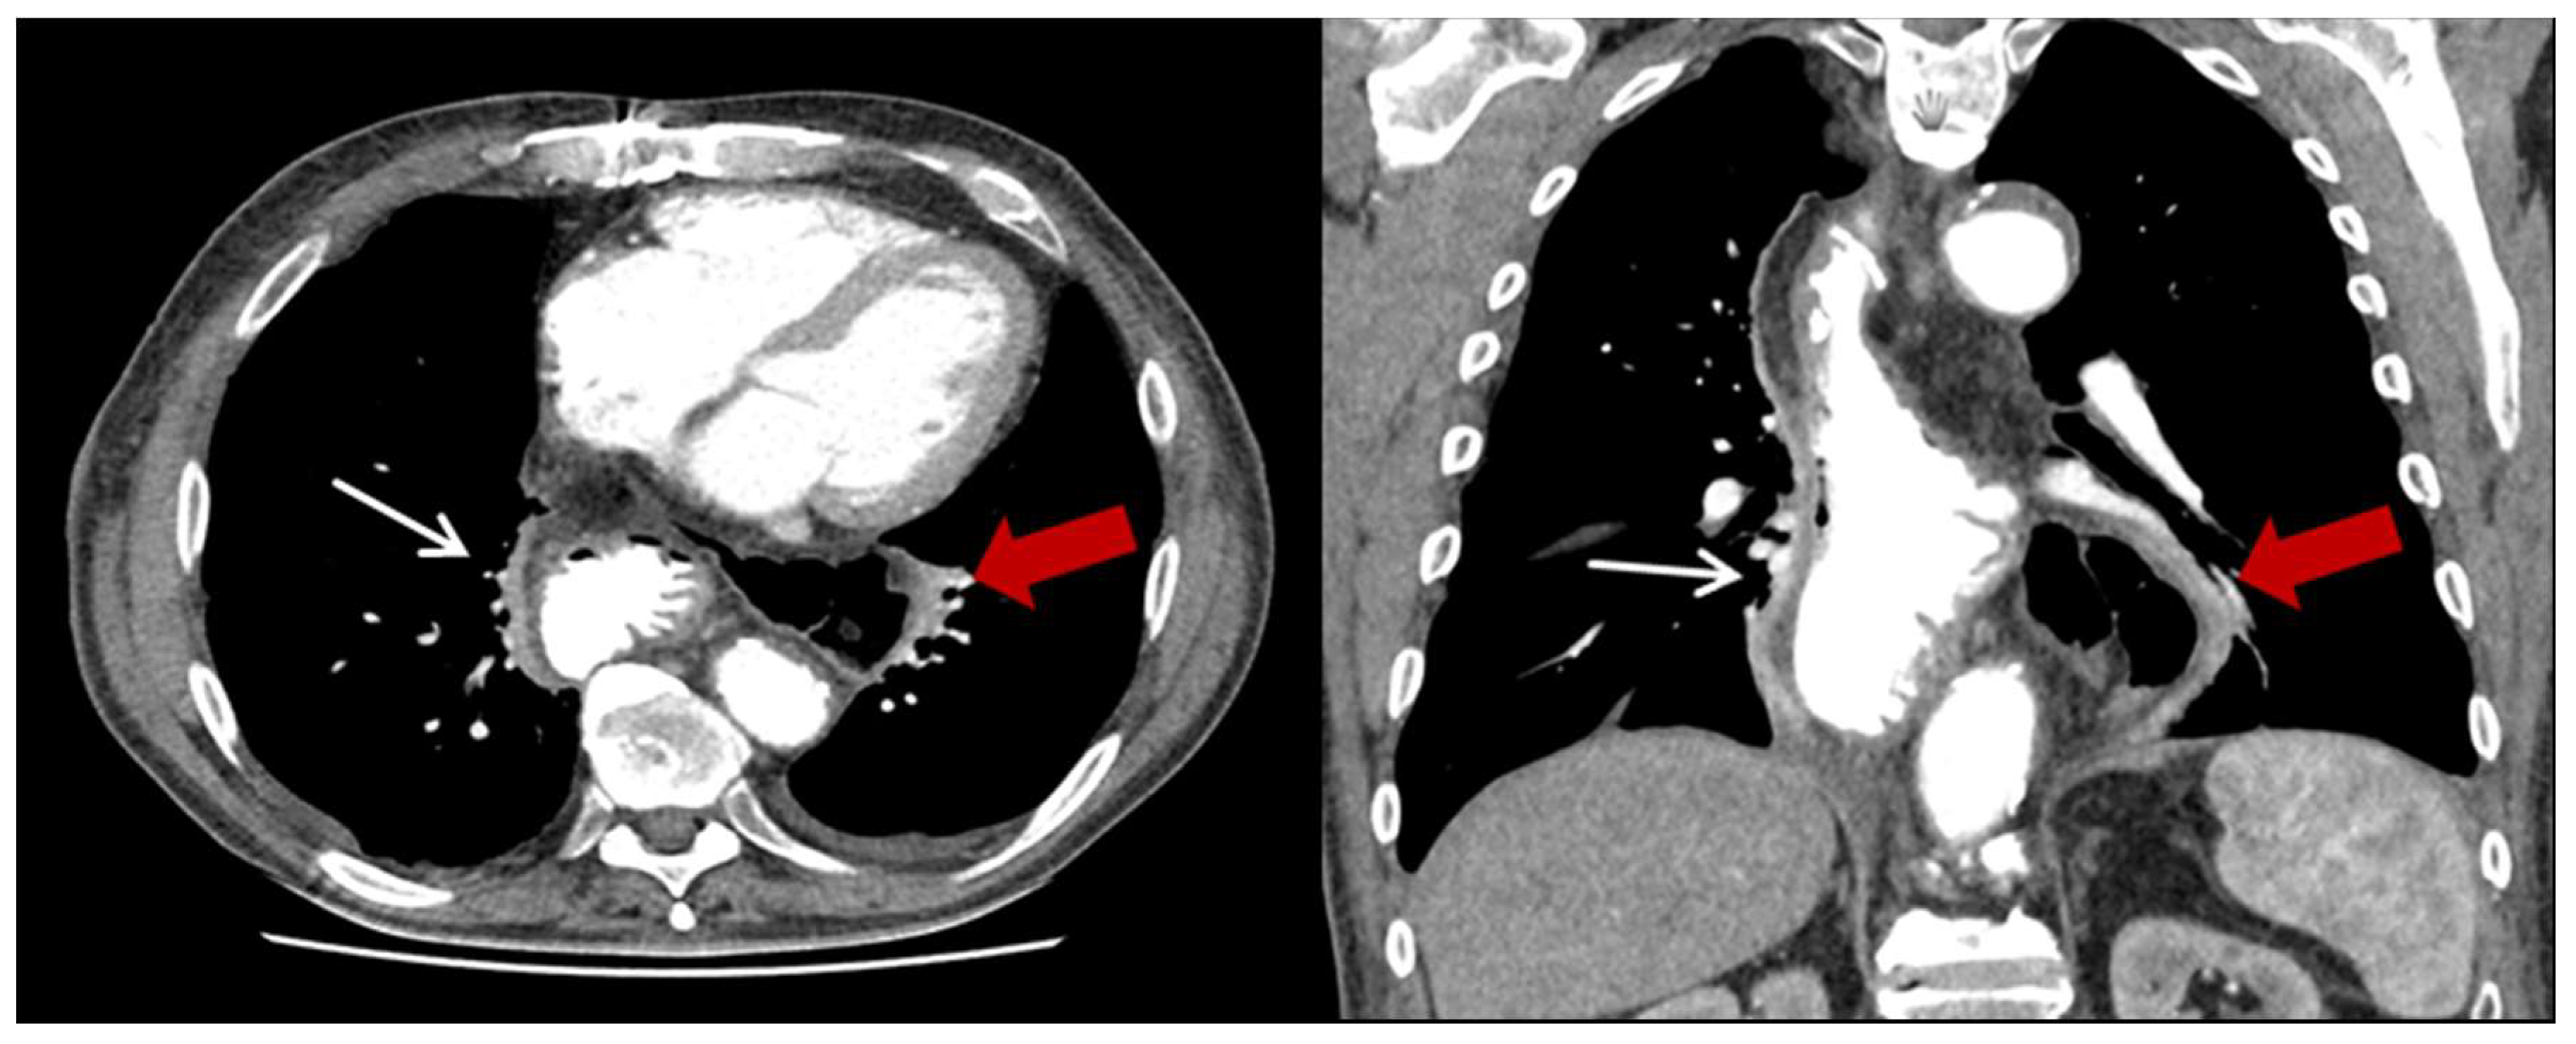

| Characteristics | HH (n = 23) (%) |

|---|---|

| Content of HH, n (%) | |

| Colon | 23 (100) |

| Additionally small bowel | 3 (13) |

| Position of the HH n (%) | |

| Left thoracic side | 18 (78.3) |

| Right thoracic side | 1 (4.4) |

| Both sides | 1 (4.4) |

| Lower mediastinum | 3 (13) |